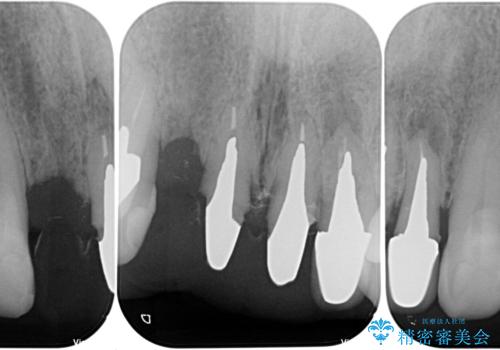

- 治療中の医院で装着した仮歯が汚れていて恥ずかしいとのことで来院された患者様です。

仮歯が不適合で歯肉が腫脹していたため、しっかりと調整した新しい仮歯にして腫れを改善した上で、オールセラミッククラウンにて補綴することとしました。

仮歯の隣の歯も詰め物の範囲が広く、仮歯をセラミックに置き換えても統一感のない口元となってしまうため、相談の結果、前歯6本をオールセラミッククラウンにて補綴治療を行うこととしました。